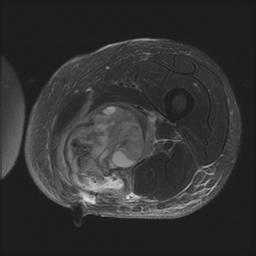

MRI